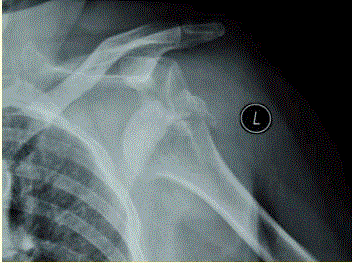

问题 患者女,58岁,左肩关节外伤,医院就诊,行X线检查,如下图。 脱位复位不成功,可能的原因是

选项 A、关节囊嵌入 B、二头肌腱嵌入 C、关节粘连 D、关节软骨退变 E、肩袖嵌入 F、移位的大结节骨块阻挡

答案 ABEF

解析 ABEF